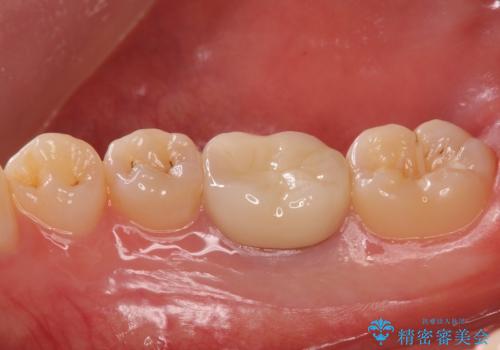

- 右下6 仮歯+ジルコニアクラウン 11,000円+110,000円費用は治療当時の料金となります

インレーにすると残った歯が薄くなってしまう場合は術後の破折リスクが高いためクラウンで修復することがあります。